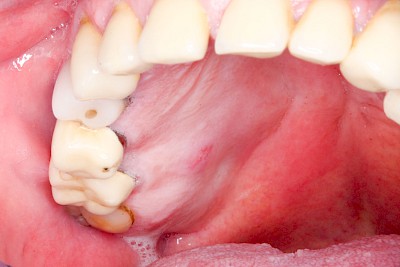

Schwellung ohne Eiter: kugelförmig

Demgegenüber entstehen Auftreibungen der Weichgewebe in Folge mechanischer Dauerreize (Reizfibrom) langsam über Wochen, Monate oder Jahre. Auch Gewohnheiten (Wangensaugen, Lippenbeißen) mit geringem Druck können als Dauerreiz in der Folge zu einer Wucherung der Weichgewebe führen. Fibrome werden nicht selten auch beobachtet in der Nähe einzelner fehlender Zähne – die Lippen oder Wangen beginnen dann, diesen Raum "aufzufüllen" (Vakatwucherung). Reizfibrome sind meist "kugelartig".